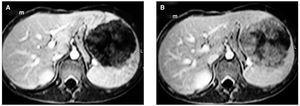

Se presenta el casode un niño de 12 años de edad que consulta porepistaxis sin causa conocida. No antecedentes hemorrágicosprevios. A la exploración, sólo se detectaesplenomegalia de dos traveses de dedo y pequeñas equimosisen regiones pretibiales. Exámenes complementarios: discretaanemia microcítica y trombocitopenia con frotis sugestivo dehiperesplenismo. TTPA alargado con factor Von Willebrand y cofactorde la ristocetina disminuidos, compatible con enfermedad de VonWillebrand. Ecografía abdominal: bazo de 14 x 11 cmcon ecoestructura heterogénea. En su interior se visualizamasa hiperecogénica con respecto al parénquimacircundante, aparentemente bien delimitada, de 9 x 9 cm yecoestructura heterogénea. Tomografía computarizada(TC) y resonancia magnética (RM): tumor esplénicobien delimitado, que aumenta realce en fases tardías delestudio dinámico (fig. 1A y B).

Figura 1.Resonancia magnética.A)Tumoraciónesplénica bien delimitada.B)Captación progresiva decontraste por parte de la masa, conforme progresa el estudiodinámico, como corresponde a una lesión de tipovascular.

Las técnicasde imagen (ecografía, TC, RM) pueden ser útiles paravalorar las características morfológicas yestructurales del tumor. Generalmente, se trata de lesionesmultinodulares que afectan al bazo de forma difusa 1,4-9; sin embargo, nuestro paciente presentaba enecografía una masa hiperecogénica bien delimitada quepudo caracterizarse como lesión de tipo vascular en TC y RM(ya que aumentaba el realce del tumor en la fase tardía delestudio dinámico). Su presentación en forma delesión única e hiperecogénica, sólo lahemos encontrado referida por un autor 9.